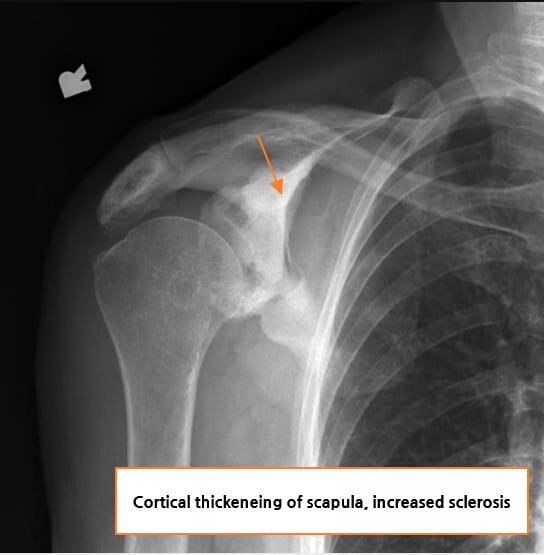

🟦 Sclerotic expansile scapula

견갑골이 비후되고 경화된 양상으로 커지며, 국소적으로 뼈의 확장이 관찰됩니다.